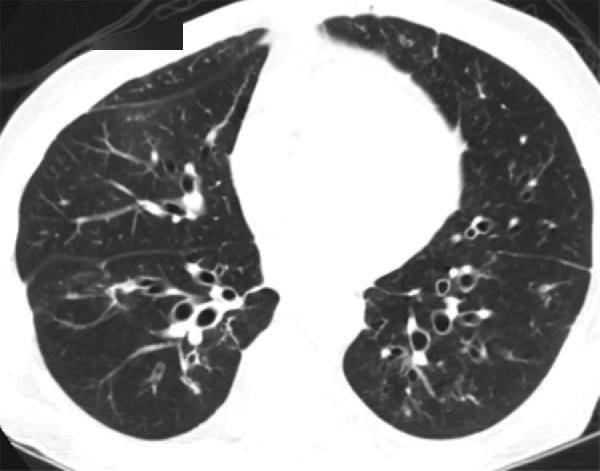

印戒征是支气管扩张ct的主要表现,是指扩张的充气支气管横截面与代表